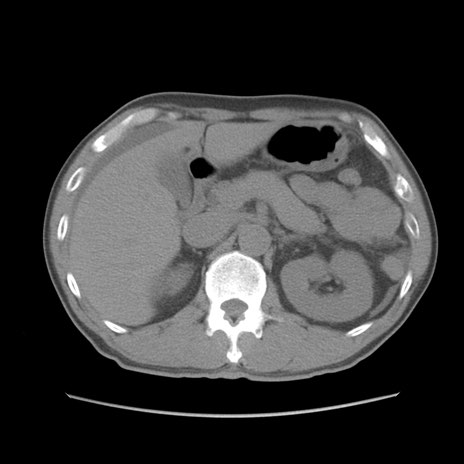

症例56 CT(横断像)

脂肪ウインドウ